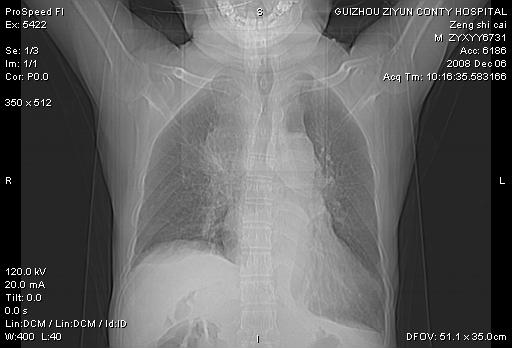

标题: CT16961:M、71岁,咳嗽半年,无血痰;胸片示右肺占位。 [打印本页]

标题: CT16961:M、71岁,咳嗽半年,无血痰;胸片示右肺占位。

右肺癌并纵隔淋巴结及胸膜转移可能性大

右肺癌并纵隔淋巴结及胸膜转移。建议气管镜

右肺纵隔型肺癌伴纵隔淋巴结及胸膜转移!

右肺纵隔型肺癌伴纵隔淋巴结转移!双侧胸水!

1)考虑右肺上叶纵隔型肺癌伴纵隔淋巴结转移。2)心包积液,双侧胸腔积液。

右肺癌并纵隔淋巴转移,腹膜后转移可能性大,两侧胸腔积液

右肺上叶纵隔型肺癌伴纵隔淋巴结转移。心包积液,双侧胸腔积液。

右上肺癌并纵隔淋巴结及胸膜转移。

右肺纵隔型肺癌伴纵隔淋巴结转移!双侧胸水\\心包积液

建议强化!主要鉴别是淋巴瘤与肺癌淋巴结转移。

右肺纵隔型肺癌伴纵隔淋巴结及胸膜转移